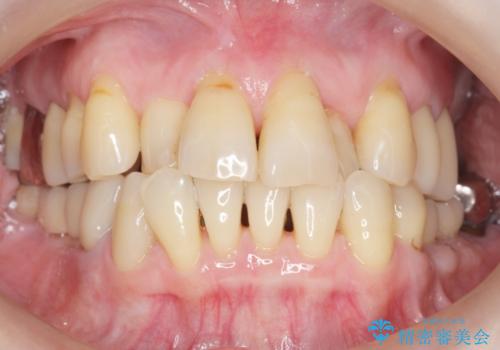

奥歯の違和感 再根管治療 40代女性

気にされていた歯の動揺や違和感がなくなり、喜んで頂けました。

モチベーションがあがり、大臼歯欠損部位の治療に関しても前向きに検討して下さるとの事でした。

クラウンの種類:オールセラミッククラウン スタンダード